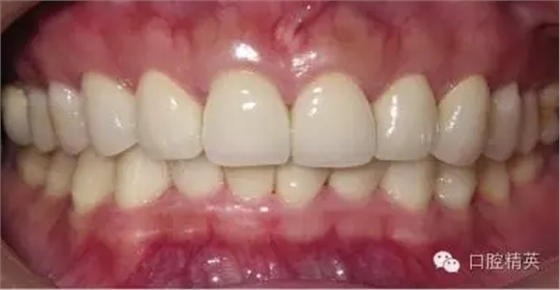

關(guān)于基礎(chǔ)治療。牙周治療和根管治療是美觀修復(fù)的基礎(chǔ)。根據(jù)術(shù)前檢查,常規(guī)先行全口潔治,必要時(shí)局部深層次的牙周治療,待牙周情況穩(wěn)定后,再考慮牙體預(yù)備與取模(見圖1、2)。在牙周炎未控制或牙齦紅腫的情況下,是不可能預(yù)備好牙齒,不可能取得清晰的印模,更談不上成功的美觀修復(fù)。

LAVA 全瓷冠強(qiáng)度高,顏色自然,邊緣高度密合,切端可見半透明感,整體效果理想,與修復(fù)前(見圖1)相比取得了醫(yī)患均滿意的效果。